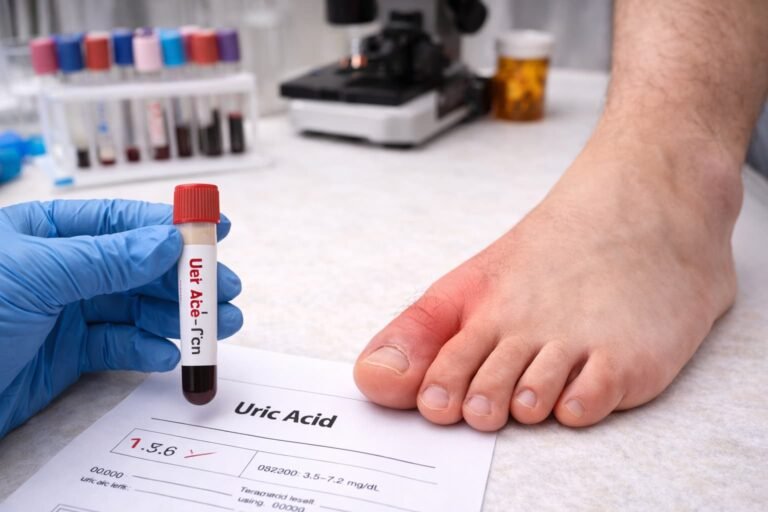

Cara mencegah asam urat yang dilakukan dengan konsisten sangat mendukung kelancaran ibadah puasa bagi setiap orang yang mengalaminya. Pengaturan pola makan yang sesuai selama bulan Ramadan dapat mengurangi kemungkinan timbulnya serangan nyeri pada sendi secara tiba-tiba.

Penderita harus memperhatikan konsumsi cairan agar proses pengeluaran racun melalui urin tetap berjalan dengan baik. Air mineral berfungsi untuk mengencerkan kadar zat limbah dalam darah sehingga tidak terjadi pembentukan kristal pada sendi.